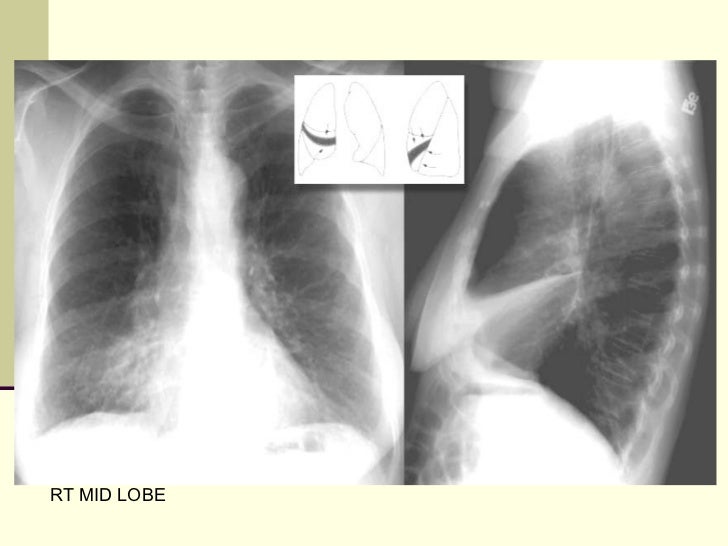

17. 17. RT MID LOBE